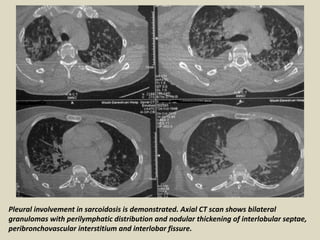

Pleural involvement in sarcoidosis is demonstrated. Axial CT scan shows bilateral

granulomas with perilymphatic distribution and nodular thickening of interlobular septae,

peribronchovascular interstitium and interlobar fissure.